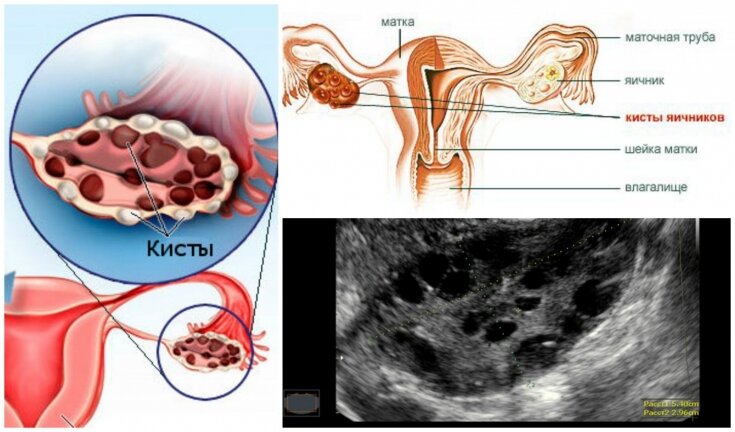

1. Киста яичника

Длительное время подобное новообразование может не давать о себе знать. Однако, в дальнейшем, когда воспаление усиливается, женщину начинают беспокоить сильнейшие резкие боли. Дискомфорт нарастает во время месячных, поскольку в этот период яичники активизируются.

Большую опасность представляет разрыв кисты: он способен не только разрушить сами яичники, но и привести к обширному внутреннему кровоизлиянию.